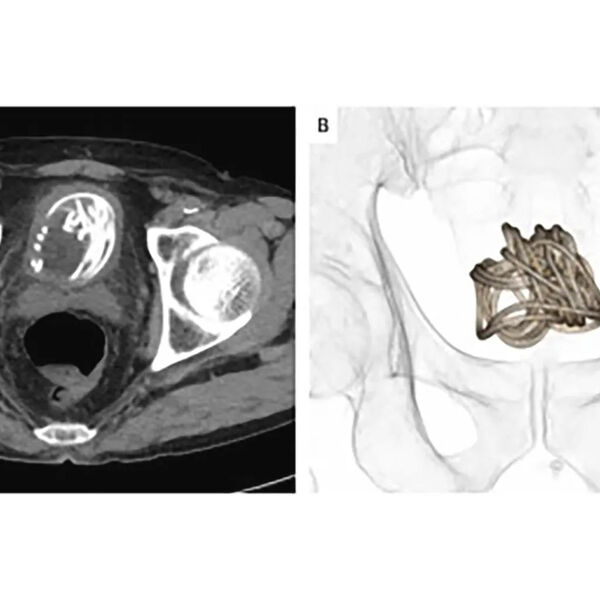

Медики хотели изъять инородное тело через уретру, однако рентген показал, что скакалка скрутилась в большой комок. В результате, чтобы вытащить веревку, хирургам пришлось разрезать мочевой пузырь.

Перед этим врачи сделали несколько подробных снимков КТ, чтобы определиться, где лучше сделать разрез. В своем отчете медики заявили, что этот инцидент продемонстрировал «неоценимую» пользу использования 3D-реконструкций для подготовки к проведению операций на мочевом пузыре.